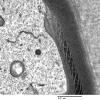

PERIPHERAL NEUROPATHY

3 NORMAL MYELIN & SCHWANN CELLS

3 Schmidt-Lanterman Clefts (2)